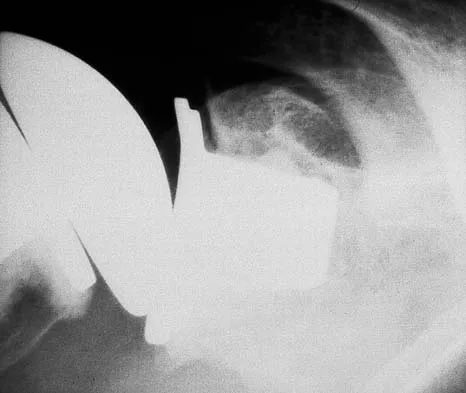

Figures 29a and 29b show the AP radiograph and CT scan of a 70-year-old man who has left thigh pain. Serum protein electrophoresis shows a monoclonal gammopathy. Additional radiographs of the femur show other lesions. Management should consist of

The underlying diagnosis is multiple myeloma. Because the patient has a large lucent lesion in the peritrochanteric region of the left proximal femur, the risk of pathologic fracture is high. Consideration should be given to prophylactic internal fixation with a locked intramedullary rod. The lesion does not appear to be a sarcoma requiring wide resection and endoprosthetic reconstruction. Neither chemotherapy nor radiation therapy alone is likely to result in long-term stabilization of the proximal femur. Postoperative treatment with bisphosphonates and radiation therapy is indicated to decrease the risk of future pathologic fractures. The patient should also be referred to a medical oncologist for medical management. Menendez LR (ed): Orthopaedic Knowledge Update: Musculoskeletal Tumors. Rosemont, IL, American Academy of Orthopaedic Surgeons, 2002, p 364.